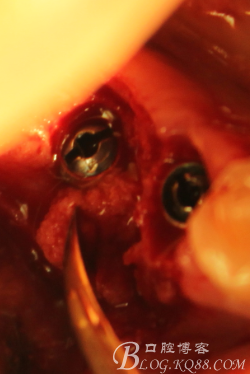

徹底搔刮肉芽,定點,正對顎尖,擴孔同期行慢轉收集自體骨

植入植體

C6頰側填入自體骨,嚴密縫合關閉創(chuàng)口